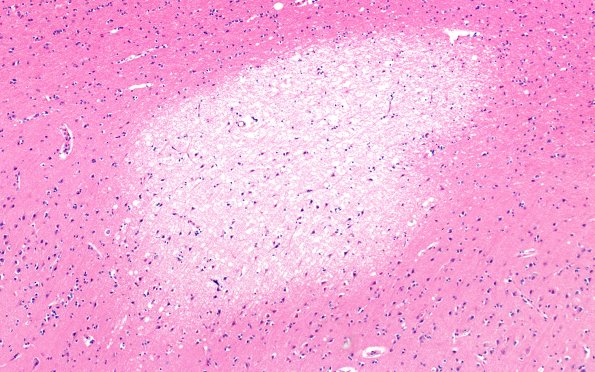

12B12 Fat Embolism (callosum) (Case 12) N13 10X

Lesions were numerous in the corpus callosum and adjacent cingulate gyrus. (H&E)